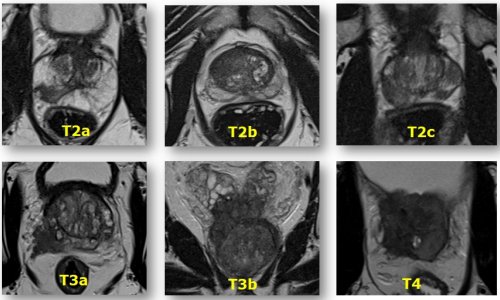

Als derzeit führendes Verfahren, um die Prostata darzustellen, gilt die multiparametrische MRT. Dabei werden morphologische Bilddaten um funktionelle Parameter ergänzt. „Funktionell bedeutet in diesem Fall zunächst einmal das Diffusionsverhalten im Gewebe“, erklärt Dr. Röthke. „Tumoren zeichnen sich durch eine hohe Zellteilungsrate aus. Wenn man sie unter dem Mikroskop betrachtet, sieht man, dass das Gewebe aus vielen großen Zellkernen und wenig Zytoplasma besteht. Dementsprechend misst man bei der diffusionsgewichteten MRT, dass sich die Wassermoleküle in diesem Gewebe weniger frei bewegen können.“ Ein weiteres funktionelles Kriterium, das mithilfe von Kontrastmitteldynamiken untersucht wird, ist das Perfusionsverhalten. Denn auch die Durchblutungsmuster von Tumoren unterscheiden sich von denen in gesundem Gewebe.

Nimmt man alle zur Verfügung stehenden radiologischen Messmethoden zusammen, dann ergibt sich eine Sensitivität um 90 Prozent. „Die diagnostische Genauigkeit ist natürlich auch untersucherabhängig“, räumt der Heidelberger Radiologe ein. „Wenn das ein Experte macht, liegt die Rate höher als bei einem unerfahrenen Befunder. Leider gibt es noch keine zertifizierten Radiologen, die eine Weiterbildung für den Bereich der Prostatabildgebung vorweisen können, wie es etwa bei der Mammographie der Fall ist. Die wird in letzter Zeit zunehmend von den überweisenden Urologen gefordert, die sich einen zuverlässigen Qualitätsstandard hinsichtlich Durchführung und Befundung der Prostata-MRT des Radiologen wünschen.“